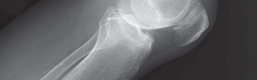

2. التصوير بالأشعة السينية (X-ray):

تُعد الأشعة السينية هي الأداة التشخيصية الأساسية لتقييم خشونة الركبة. يلتقط الأستاذ الدكتور هطيف صورًا للركبة من زوايا مختلفة، بما في ذلك صور الوقوف (Weight-bearing X-rays)، والتي تُظهر المفصل تحت تأثير وزن الجسم الطبيعي. تُظهر الأشعة السينية ما يلي:

- تضييق المسافة المفصلية: خاصة في الجانب الإنسي للركبة، مما يشير إلى تآكل الغضروف.

- تكون النتوءات العظمية (Osteophytes): وهي نتوءات عظمية صغيرة تتشكل حول حواف المفصل نتيجة للتآكل.

- تغيرات في كثافة العظام: مثل التصلب تحت الغضروفي (Subchondral Sclerosis).

- درجة الانحراف التقوسي: قياس الزوايا المحورية للساق لتحديد مدى التقوس بدقة.